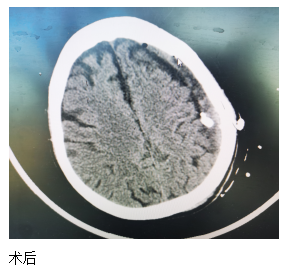

近日,一位84歲高齡患者來(lái)江寧中院就診,表現(xiàn)為:右側(cè)肢體的力量下降、不能獨(dú)立站立、言語(yǔ)不利、吐字不清。經(jīng)頭部CT檢查發(fā)現(xiàn),患者左側(cè)大面積慢性硬膜下血腫,嚴(yán)重壓迫腦組織。

患者收入院后,完善各項(xiàng)檢查,無(wú)明顯手術(shù)禁忌,中醫(yī)院神經(jīng)外科團(tuán)隊(duì)經(jīng)過(guò)精心周全的準(zhǔn)備,為其實(shí)施了腦膜中動(dòng)脈栓塞結(jié)合硬通道血腫穿刺引流的復(fù)合手術(shù)。術(shù)后第二天,患者肢體無(wú)力的癥狀得到了明顯改善,語(yǔ)言表達(dá)也恢復(fù)如初。患者及家屬對(duì)此治療效果非常滿意。